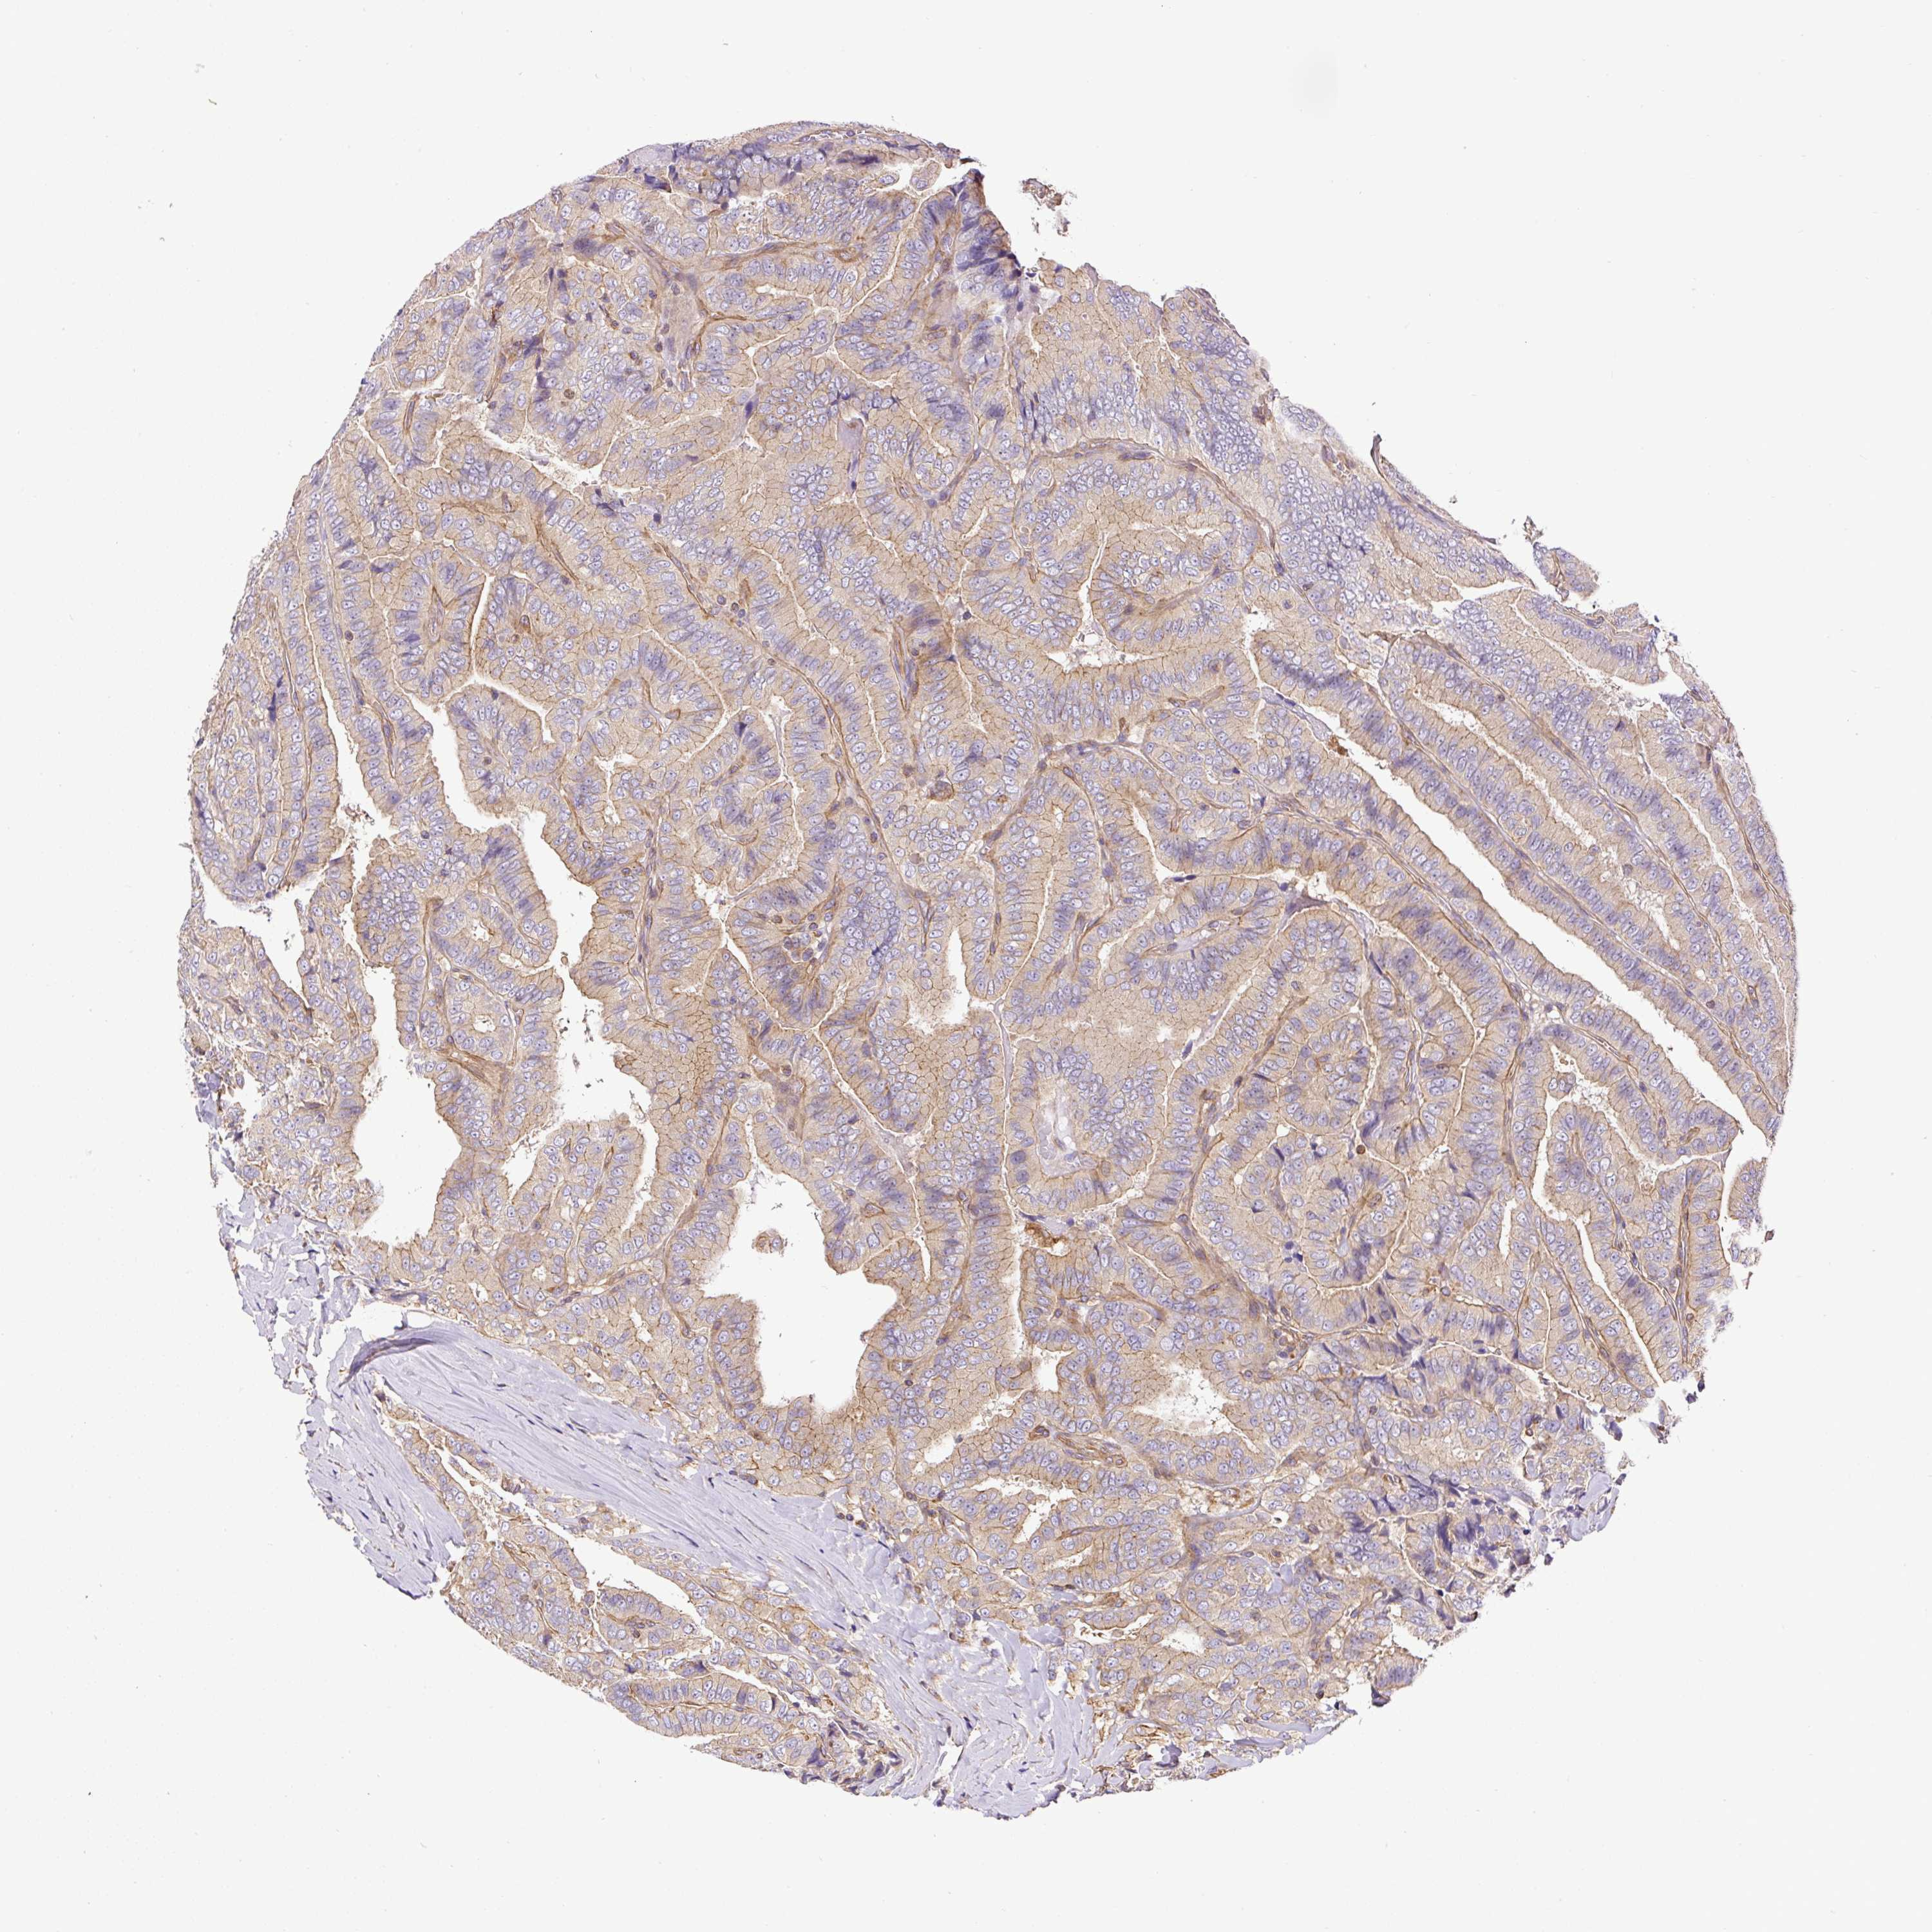

THYROID CANCER - Protein expressioni

A mouse-over function shows sample information and annotation data. Click on an image to view it in a full screen mode. Samples can be filtered based on level of antibody staining by selecting one or several of the following categories: high, medium, low and not detected. The assay and annotation is described here.

Note that samples used for immunohistochemistry by the Human Protein Atlas do not correspond to samples in the TCGA dataset.

Antibody stainingi

Antibody staining in the annotated cell types in the current human tissue is reported as not detected, low, medium, or high, based on conventional immunohistochemistry profiling in selected tissues. This score is based on the combination of the staining intensity and fraction of stained cells.

Each image is clickable and will lead to virtual microscopy that enables deeper exploration of all samples and also displays staining intensity scores, fraction scores and subcellular localization as well as patient and tissue information for each sample.

Antibody HPA071875

Staining

High

Medium

Low

Not detected

Intensity

Strong

Moderate

Weak

Negative

Quantity

>75%

75%-25%

<25%

None

Location

Nuclear

Cytoplasmic/membranous

Cytoplasmic/membranous,nuclear

Papillary adenocarcinoma, NOS

Follicular adenoma carcinoma, NOS